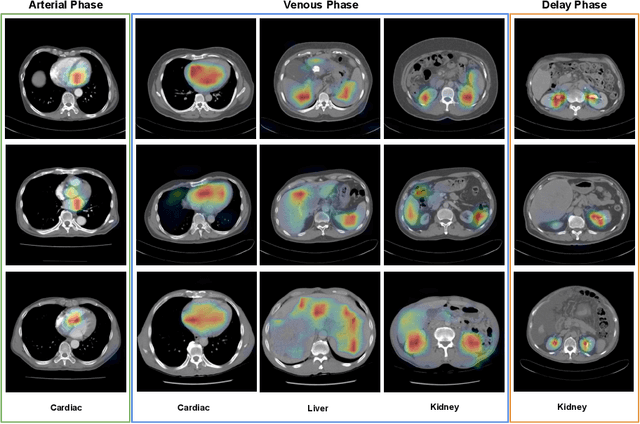

Abstract:Hepatocellular carcinoma (HCC) can be potentially discovered from abdominal computed tomography (CT) studies under varied clinical scenarios, e.g., fully dynamic contrast enhanced (DCE) studies, non-contrast (NC) plus venous phase (VP) abdominal studies, or NC-only studies. We develop a flexible three-dimensional deep algorithm, called hetero-phase volumetric detection (HPVD), that can accept any combination of contrast-phase inputs and with adjustable sensitivity depending on the clinical purpose. We trained HPVD on 771 DCE CT scans to detect HCCs and tested on external 164 positives and 206 controls, respectively. We compare performance against six clinical readers, including two radiologists, two hepato-pancreatico-biliary (HPB) surgeons, and two hepatologists. The area under curve (AUC) of the localization receiver operating characteristic (LROC) for NC-only, NC plus VP, and full DCE CT yielded 0.71, 0.81, 0.89 respectively. At a high sensitivity operating point of 80% on DCE CT, HPVD achieved 97% specificity, which is comparable to measured physician performance. We also demonstrate performance improvements over more typical and less flexible non hetero-phase detectors. Thus, we demonstrate that a single deep learning algorithm can be effectively applied to diverse HCC detection clinical scenarios.

Abstract:As the demand for more descriptive machine learning models grows within medical imaging, bottlenecks due to data paucity will exacerbate. Thus, collecting enough large-scale data will require automated tools to harvest data/label pairs from messy and real-world datasets, such as hospital PACS. This is the focus of our work, where we present a principled data curation tool to extract multi-phase CT liver studies and identify each scan's phase from a real-world and heterogenous hospital PACS dataset. Emulating a typical deployment scenario, we first obtain a set of noisy labels from our institutional partners that are text mined using simple rules from DICOM tags. We train a deep learning system, using a customized and streamlined 3D SE architecture, to identify non-contrast, arterial, venous, and delay phase dynamic CT liver scans, filtering out anything else, including other types of liver contrast studies. To exploit as much training data as possible, we also introduce an aggregated cross entropy loss that can learn from scans only identified as "contrast". Extensive experiments on a dataset of 43K scans of 7680 patient imaging studies demonstrate that our 3DSE architecture, armed with our aggregated loss, can achieve a mean F1 of 0.977 and can correctly harvest up to 92.7% of studies, which significantly outperforms the text-mined and standard-loss approach, and also outperforms other, and more complex, model architectures.